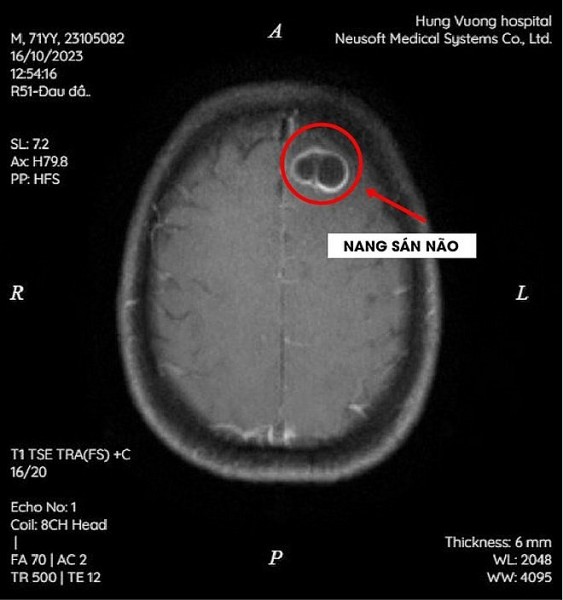

Phú Thọ: Thói quen ăn tiết canh khiến sán làm tổ trong não

16:30 | 30/11/2023